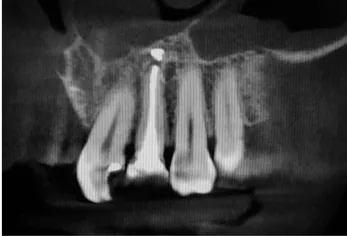

Technika odbudowy kostnej stosowana w celu wszczepienia implantów w zanikłe, boczne odcinki szczęk. Najistotniejszą przyczyną utraty kości wyrostka zębodołowego szczęk w odcinkach bocznych są ekstrakcje zębów. Niedostatek kości w wymiarze pionowym stanowi szczególną anatomiczną przeszkodę dla implantacji w okolicy dna zatoki szczękowej. Chcąc odbudować uzębienie i przywrócić funkcję żucia, trzeba podjąć wieloetapowe leczenie rekonstrukcyjne.

Zabiegiem, który rozwiązuje ten problem, jestpodniesienie dna zatoki szczękowej (sinus lift), czyli odbudowa kostna w okolicy zębów trzonowych. Ubytek kości uzupełniany jest materiałem kościotwórczym, który układany jest pod błoną wyścielającą zatokę szczękową, zwaną membraną Schneidera. Zmniejszając objętość zatoki szczękowej, tworzy się tym samym stabilną strukturę kostną, umożliwiającą zabieg implantacji wszczepów śródkostnych.